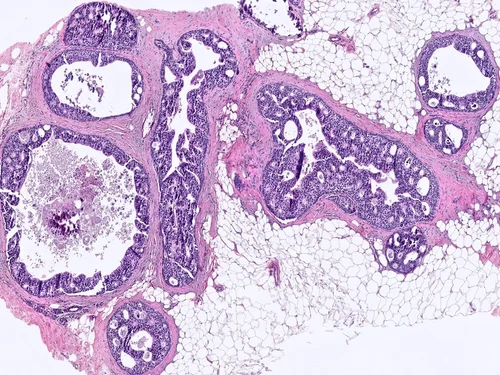

Encapsulated Papillary Carcinoma